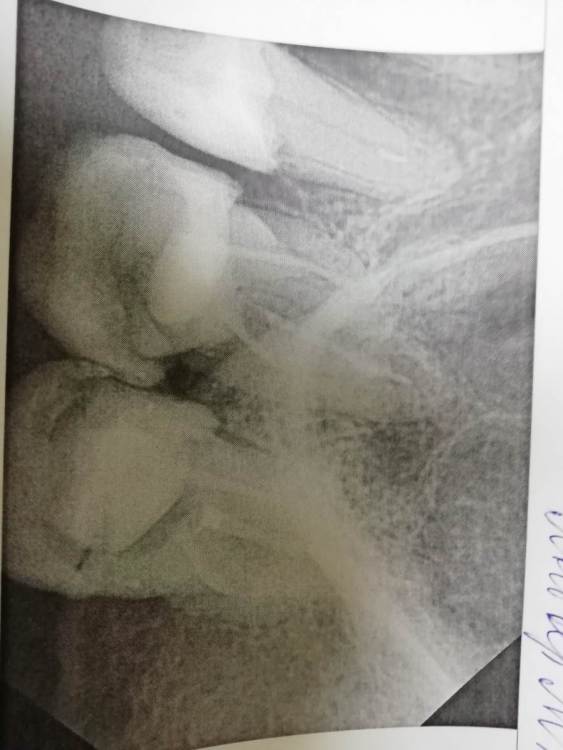

laz2000 Опубликовано 23 марта, 2021 Поделиться Опубликовано 23 марта, 2021 Занялся лечением зубов. 25 зуб мне должны были запломбировать каналы, поставить штифт и поставить световую пломбу. 26 и 27 зуб — пока только пролечены и запломбированы каналы. Несколько вопросов: 1. насколько качественно запломбированы каналы 26 и 27 зуба? (Врач почему то сказал может быть надо будет каналы в 26 зубе уплотнять, но будет думать) 2. 25 зуб — запломбированы ли каналы этого зуба вообще? 3. 25 зуб — установлен ли штифт? Во вложенных файлах снимки этих трех зубов. Ссылка на комментарий

red_butler Опубликовано 24 марта, 2021 Поделиться Опубликовано 24 марта, 2021 качество снимков не позволяет дать полноценные ответы, кроме всего нужен очный осмотр. В зависимости от степени разрушения, или протезировать искусственными коронками, или удалять Ссылка на комментарий

red_butler Опубликовано 26 марта, 2021 Поделиться Опубликовано 26 марта, 2021 2 часа назад, laz2000 сказал: Извините, Скажите пожалуйста Вы уверены, что каналы 25 зуба полностью запломбированы? Вы читали что я сказал что ваши снимки плохие???? Я вижу в канале следы пломбировочного материала. Покажите снимки нормального качества, в идеале срезы Кт, и фото во рту. Пока предположительный прогноз по Впшим зубам- плохой Ссылка на комментарий